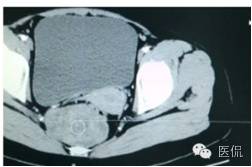

增强静脉期(CT值62HU)